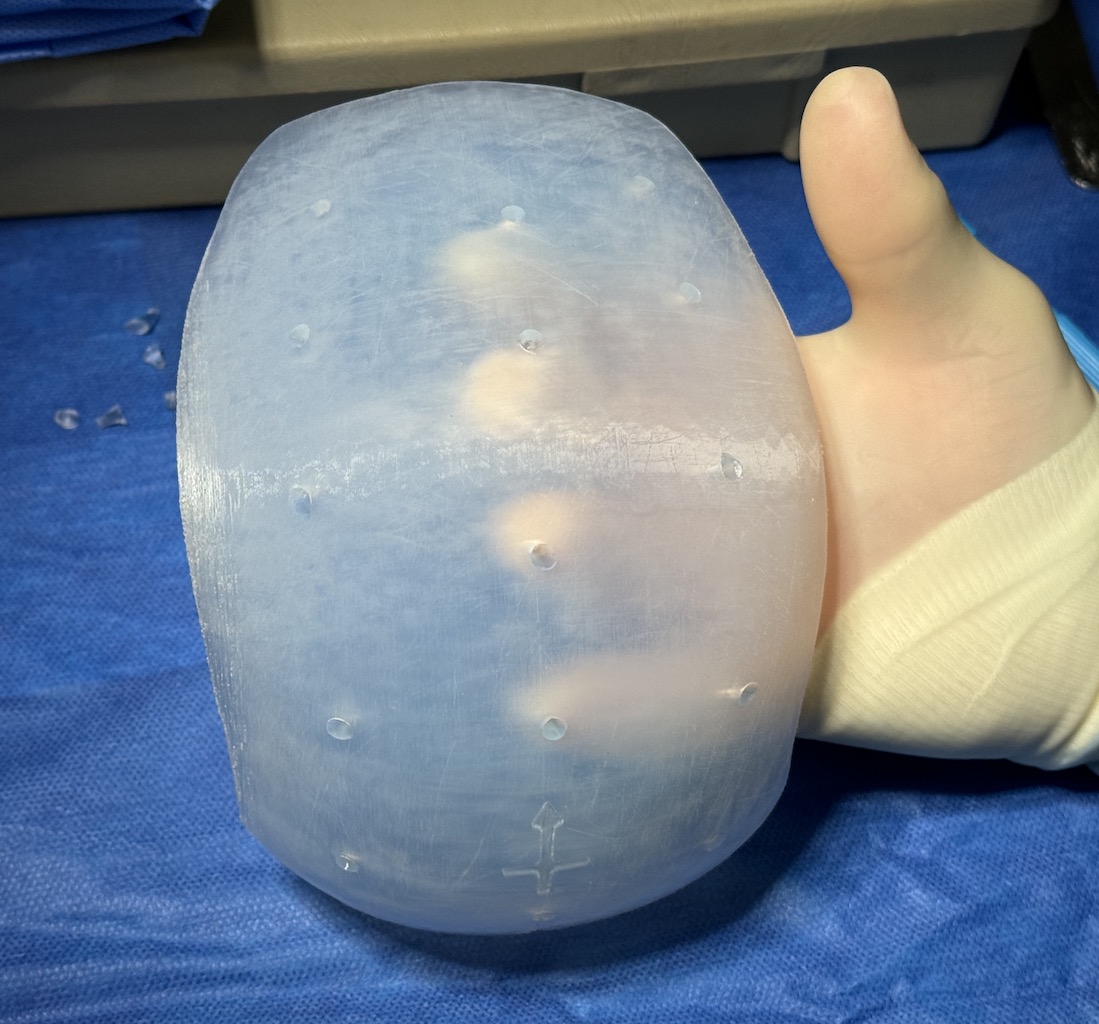

Desire for large overall skull augmentation procedure. Two piece custom skull implant designed with 250ccs volume.

1st stage scalp expander placed and inflated to 225ccs. 2nd stage two piece skull implant placed 4 months later.

Desire for large overall skull augmentation procedure. Two piece custom skull implant designed with 250ccs volume.

1st stage scalp expander placed and inflated to 225ccs. 2nd stage two piece skull implant placed 4 months later.